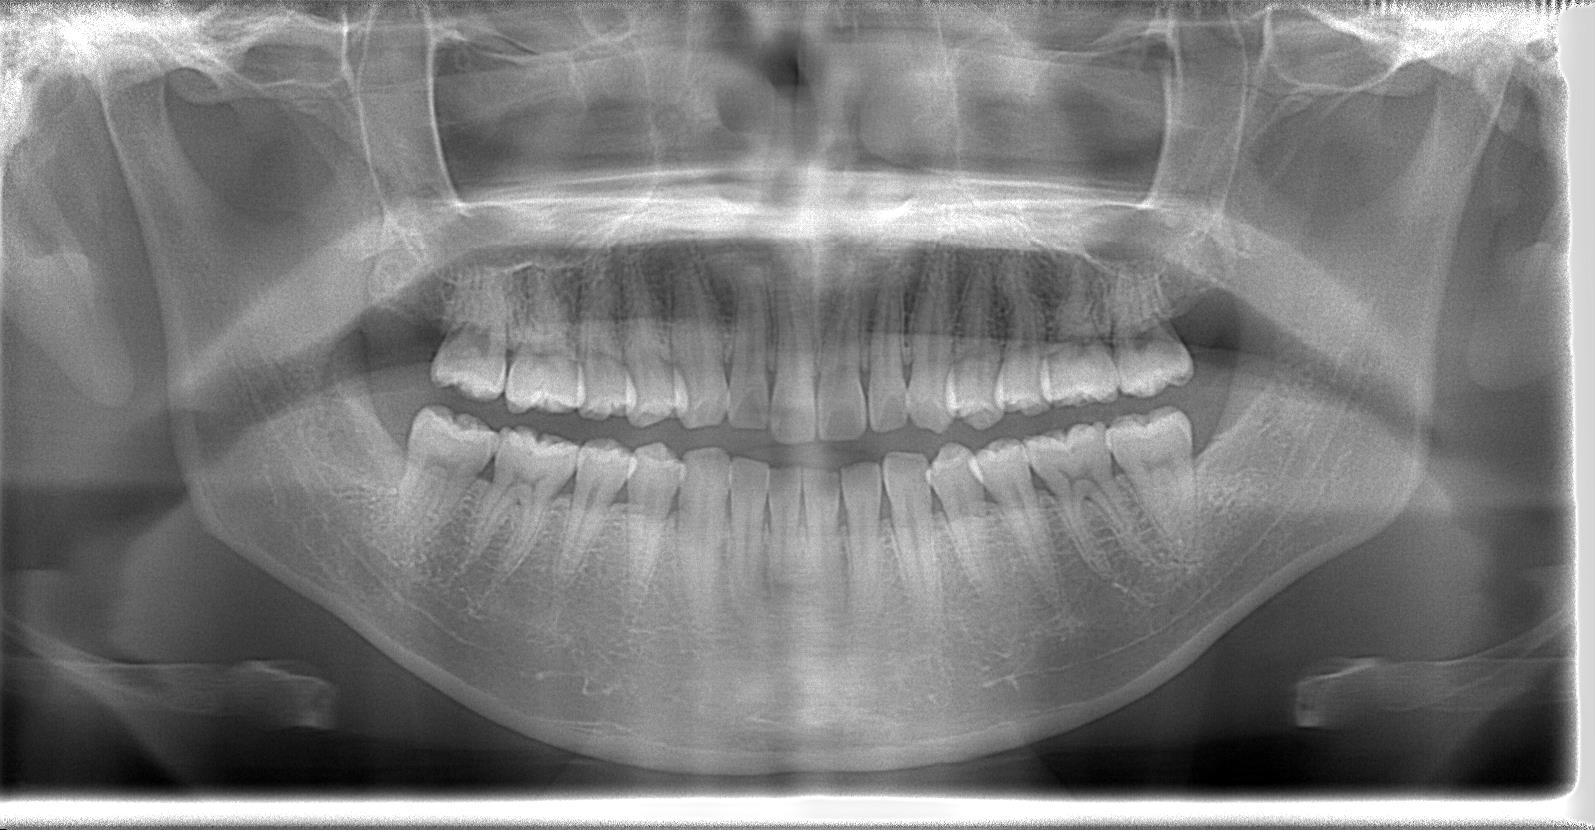

レントゲン写真の状態を御覧ください。

術前パノラマ写真

術後パノラマレントゲン写真

抜歯後、経過良好です。